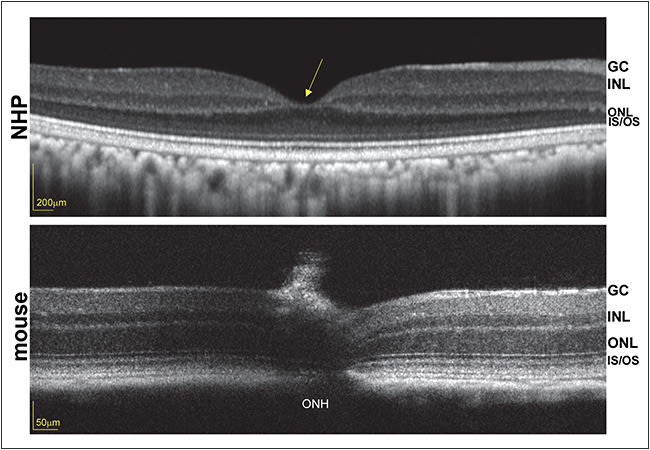

Because the disease target is the foveal cones, and unlike primates, mice lack a fovea (Figure 2), work is under way to characterize therapy in an all-cone model of retGC1 deficiency. Genzyme recently partnered with investigators at the University of Florida/University of Pennsylvania to conduct the final preclinical and safety studies necessary to file an IND and to initiate phase 1/2 clinical trials to evaluate the safety and efficacy of an AAV-based strategy for GUCY2D-LCA1.

Figure 2. Optical coherence tomography scans of nonhuman primate (top) and mouse (bottom) retinas, obtained with Heidelberg Spectralis (Carlsbad, CA) and Bioptigen (Durham, NC), respectively. Foveal pit in the primate (yellow arrow) is absent from the mouse retina. ONH = optic nerve head, ONL = outer nuclear layer, INL = inner nuclear layer, GC = ganglion cell, IS/OS = inner segment/outer segment.

Both rational design and directed evolution techniques have been used to design novel AAV capsid variants that exhibit increased photoreceptor transduction from the mouse vitreous.54,55 Their translation to NHP has proved challenging, however, due in part to anatomical differences between mouse and NHP eyes (Figure 2, page 22), dilution effects (higher vitreous volume in primates), and immunological differences across species. Further modifications to both AAV capsid and genome are being explored to overcome these hurdles.